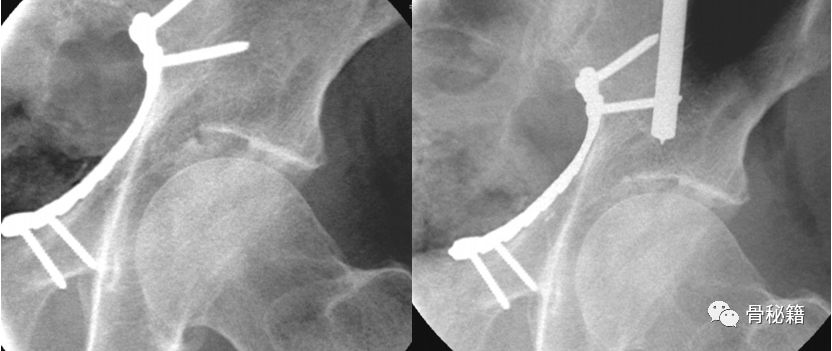

髂腹股沟入路

改良入路